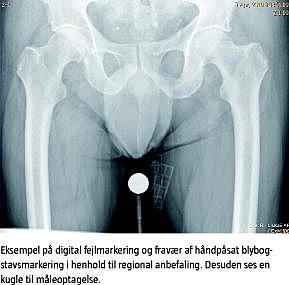

Sidemarkeringen af røntgenoptagelser hører med som et vigtigt standardelement i alle røntgenoptagelser, og i den nye regionale vejledning anbefales håndpåsat blybogstavsmarkering placeret så tæt på patienten som muligt, men i tilfælde af forglemmelse, eller hvis en særlig situation har umuliggjort håndpåsat blybogstavsmarkering, vil efterfølgende digital sidemarkering også være rigtig og skal være påført optagelsen, inden denne sendes til PACS.